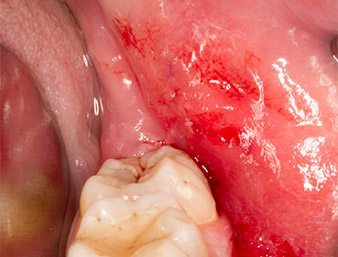

Seis meses después de una osteotomía del diente 38, un paciente de 26 años padecía dolores repetitivos en la zona de la operación y se quejaba de hipersensibilidad en la zona de extensión del nervio alveolar inferior. El odontólogo que lo remitió, y que no era quien había realizado la extracción dental original, lo envió al departamento de cirugía oral de la Clínica Dental Universitaria de Viena.

Ya en la ortopantomografía, se constató que había un resto radicular de la región 38 muy cerca del nervio alveolar inferior (figura 1). La raíz se había fracturado durante la osteotomía, pero el primer odontólogo que había tratado al paciente no había extraído esta debido a la presencia de dolor durante la operación.

Ortopantomografía

Imagen 1: Ortopantomografía 6 meses después de la osteotomía del diente 38: el resto radicular se encontraba cerca del nervio alveolar inferior.

La anamnesis del paciente era favorable (no fumador, 26 años) para garantizar el éxito de la aplicación. Como la ortopantomografía mostró que el resto radicular se encontraba muy cerca del nervio alveolar inferior, se realizó también una tomografía volumétrica digital (6).